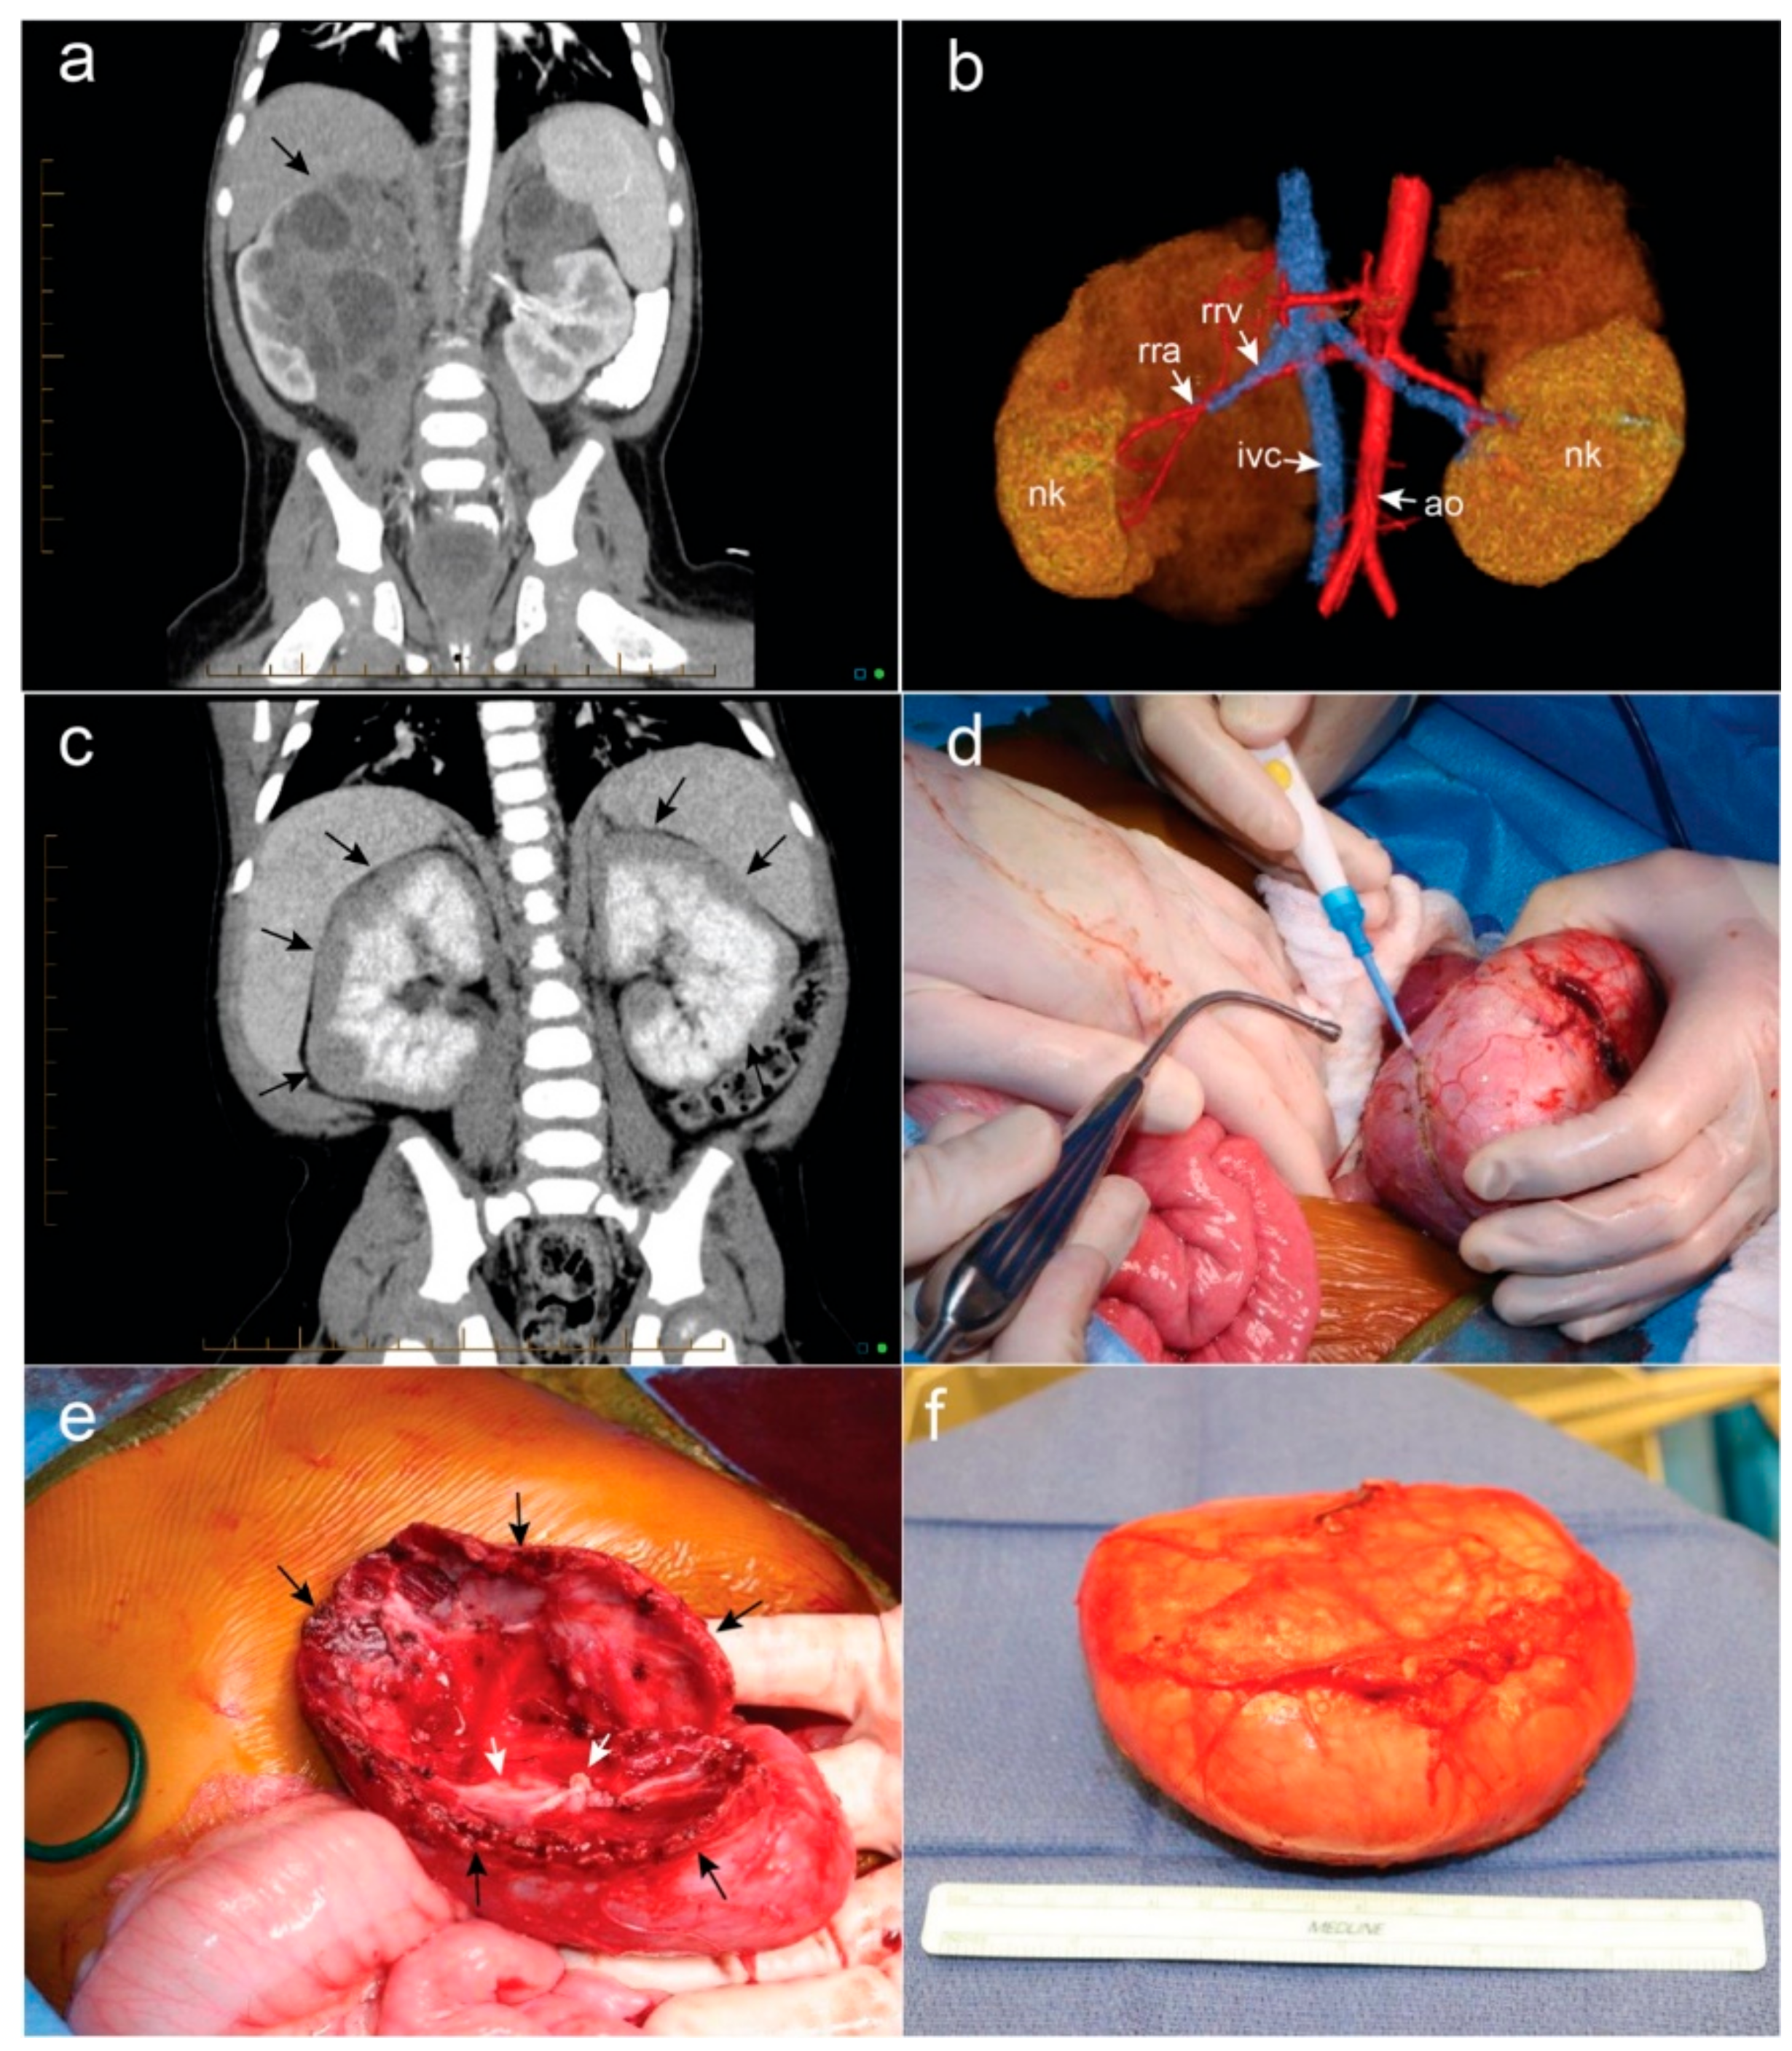

- Giron-Vallejo, O.; Garcia-Calderon, D.; Ruiz-Pruneda, R.; Cabello-Laureano, R.; Domenech-Abellan, E.; Fuster-Soler, J.L.; Ruiz-Jimenez, J.I. Three-dimensional printed model of bilateral Wilms tumor: A useful tool for planning nephron sparing surgery. Pediatr. Blood Cancer 2018, 65, e26894. [Google Scholar] [CrossRef] [PubMed]